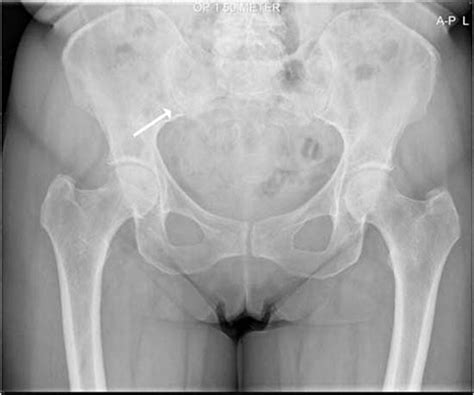

Diagnosing an SIF requires a high index of suspicion from healthcare providers, as standard X-rays often miss these fractures, especially in the early stages. More advanced imaging is typically necessary to confirm the diagnosis.

Imaging Modality Effectiveness for SIF

X-Ray Low sensitivity; often shows normal results even when a fracture exists.

MRI Gold standard; highly sensitive in detecting bone marrow edema and fracture lines.

CT Scan Good for visualizing the fracture line, but less sensitive than MRI for early stages.

Bone Scan Sensitive, but provides less anatomical detail than MRI or CT.